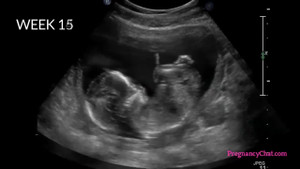

Tiến trình thai nhi lớn lên từ khi trứng gặp tinh trùng

Sự phát triển của thai nhi trong bụng mẹ là một điều vô cùng kỳ diệu, nhưng đã bao giờ bạn thử tưởng tượng và so sánh sự phát triển của em bé trong bụng mẹ với những loại hoa quả trái cây chưa?